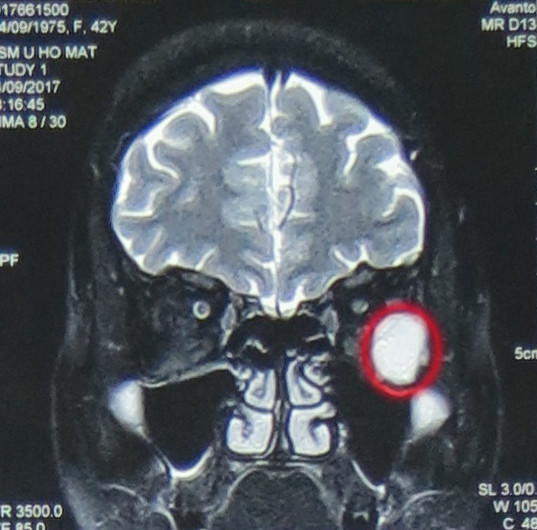

Qua thăm khám, các bác sĩ đã chẩn đoán, bệnh nhân N.T.M.T. bị u hốc mắt trái, kích thước 21x17x23mm, khối gây đè đẩy các cơ vận nhãn, nhãn cầu và dây thần kinh thị giác vào trong làm lồi nhãn cầu trái độ I. Các bác sỹ khoa Phẫu thuật Thần kinh I đã hội chẩn và tiến hành phẫu thuật nội soi cắt u hốc mắt cho bệnh nhân qua đường mũi.

Phẫu thuật nội soi lấy khối u hốc mắt qua đường mũi ảnh 1Hình ảnh phim chụp cho thấy, bệnh nhân N.T.M.T có khối u hốc mắt trái, kích thước 21x17x23mm